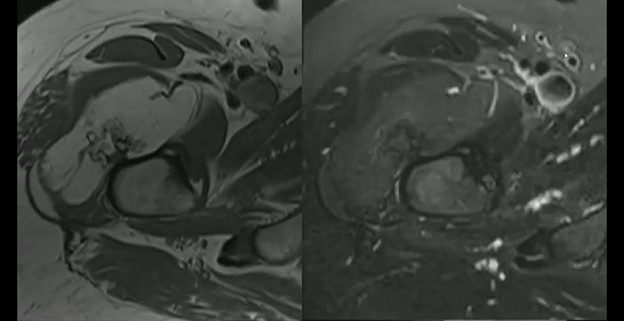

Imaging: Two views of an unusual surface lesion coming from the femur. Bone exostosis is evident. On the right, it doesn’t appear there’s any communication with the marrow space. Looking at soft tissues, you can make out a large, low-density mass—sort of draped below that little piece of bone coming off of the cortex.

CT shows the bone exostosis corresponds with this lesion coming from the surface of the cortex. It does *not* involve the medullary space; it doesn’t extend through the cortex. That low-density mass corresponds with this very fatty mass atop the bone.

Sure, there are a few septations, but no other suspicions.

DDX? This combination of a benign fatty mass attached to the underlying bone surface is a parosteal lipoma.